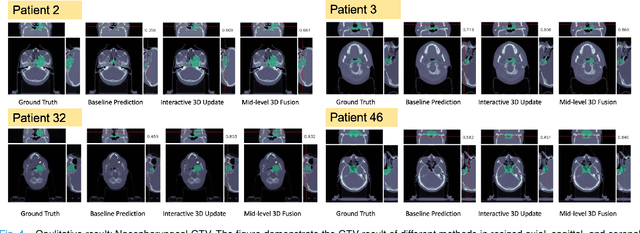

Abstract:Gross tumor volume (GTV) delineation on tomography medical imaging is crucial for radiotherapy planning and cancer diagnosis. Convolutional neural networks (CNNs) has been predominated on automatic 3D medical segmentation tasks, including contouring the radiotherapy target given 3D CT volume. While CNNs may provide feasible outcome, in clinical scenario, double-check and prediction refinement by experts is still necessary because of CNNs' inconsistent performance on unexpected patient cases. To provide experts an efficient way to modify the CNN predictions without retrain the model, we propose 3D-fused context propagation, which propagates any edited slice to the whole 3D volume. By considering the high-level feature maps, the radiation oncologists would only required to edit few slices to guide the correction and refine the whole prediction volume. Specifically, we leverage the backpropagation for activation technique to convey the user editing information backwardly to the latent space and generate new prediction based on the updated and original feature. During the interaction, our proposed approach reuses the extant extracted features and does not alter the existing 3D CNN model architectures, avoiding the perturbation on other predictions. The proposed method is evaluated on two published radiotherapy target contouring datasets of nasopharyngeal and esophageal cancer. The experimental results demonstrate that our proposed method is able to further effectively improve the existing segmentation prediction from different model architectures given oncologists' interactive inputs.